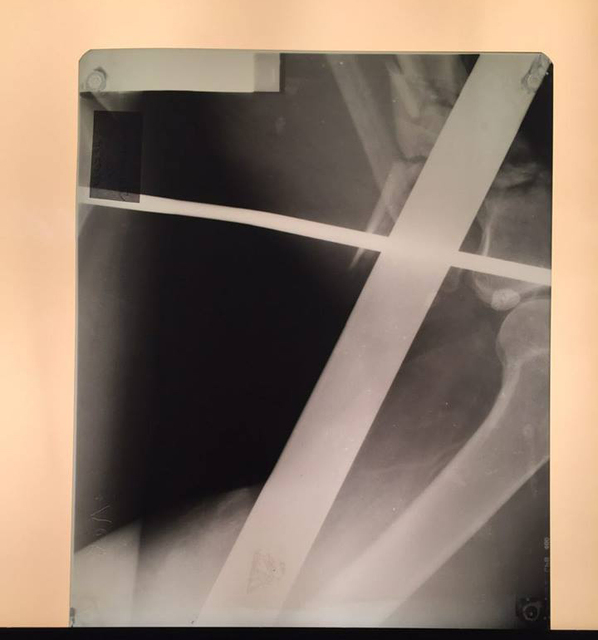

Заведующий приемно-диагностического отделения больницы имени Мечникова Петр Давыденко рассказал, что металлический профиль буквально насквозь проткнул мужчину.

«Итог: инородное тело левой голени, левого бедра, левой половины таза, левой половины поясничной области, открытый многооскольчатый перелом верхней трети левой большеберцовой кости, травматический шок», — отметил врач.

Первую медицинскую помощь пострадавшему оказали в Царичанке, после чего мужчину доставили в Мечникова. Осмотр немедленно провели дежурные травматологи, урологи, хирурги и нейрохирурги. Провели операцию по удалению инородного тела, ПХО ран, лапароцентез, а также объемное переливание препаратов крови.

Пострадавшего госпитализировали в реанимационное отделение. По словам Петра Давыденко, внутренние жизненно важные органы и магистральные сосуды чудом не повреждены. Состояние пациента тяжелое, но стабильное.